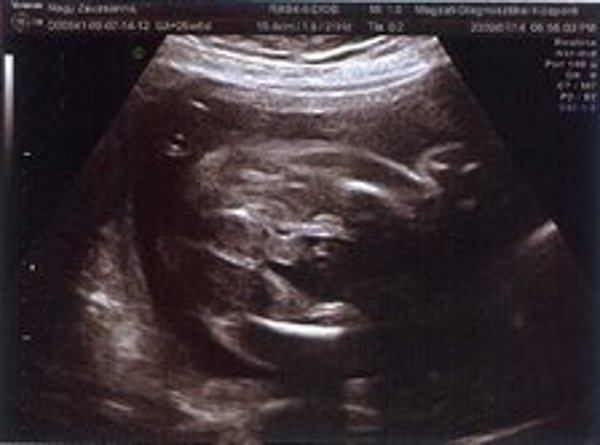

Kistörpe! Tényleg nagyon rohan az idő. Gratula Nektek! Majd hozz képet az uh-ról!